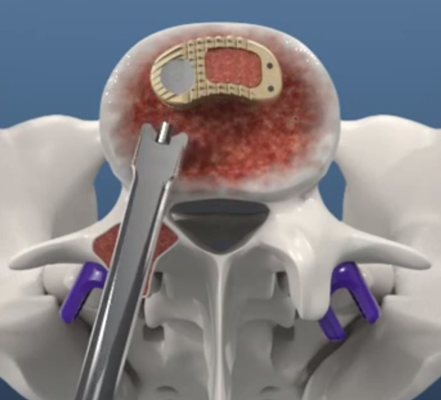

Astfel, în urma unui număr mare de investigaţii suplimentare, a fost luată decizia de a folosi un abord chirurgical numit ”fuziune intervertebrală transforaminală”. Tehnica dată este mai complicată şi mai solicitantă faţă de dotarea tehnică a blocului de operaţii şi a abilităţilor echipei chirurgicale, însă oferă un şir de avantaje pentru pacient.

Deoarece pacientul a fost operat anterior de 2 ori, utilizarea aceluiaşi coridor chirurgical tradiţional putea fi însoţită de un risc mare de leziuni a nervilor şi vaselor în canalul spinal. De aceea, a fost aleasă o cale mai puţin utilizată în practica cotidiană, dar care a fost cea mai raţională pentru pacientul dat, aşa-numitul abord paramedian transmuscular sau abordul prin spaţiul Wiltse.

Pacientul s-a bucurat de un parcurs postoperator favorabil. Imediat după operaţie, au dispărut durerile pronunţate din picior, s-a ameliorat sensibilitatea şi capacitatea de control asupra mişcărilor în piciorul afectat. A doua zi, pacientul a fost mobilizat şi a făcut primii paşi, iar peste încă 2 zile a început procesul de reabilitare activă. Ameliorarea importantă a durerilor şi a dereglărilor de mers a dus la faptul că la a 3-a zi după operaţie, pacientul a abandonat suportul cu cârje, fiind lăsate în secţie ca amintire. Peste 7 zile postoperator, a fost externat în stare satisfăcătoare.

Este un caz fericit pentru pacientul din Italia şi de succes pentru secţia Neurochirurgie, dar şi pentru întreaga instituţie medicală, or, astfel de intervenţii complicate au devenit posibile în Republica Moldova în urma deschiderii noului Bloc chirurgical în luna mai curent, prin intermediul căruia ţara noastră a obţinut facilităţi şi posibilităţi care au existat pînă nu demult doar în centrele medicale contemporane performante din lume. Astfel, sala de operaţii Hybrid a blocului dispune de metode de neuroimagistică intraoperatorie şi sisteme de monitoring şi neuronavigaţie, sisteme specializate de implanturi din titan şi instrumente chirurgicale, echipamente pentru disecţie osoasă. Acest complex chirurgical este completat de un departament ultradotat de anestezie şi neuroreanimare, care asigură o parcurgere perioperatorie fără complicaţii.